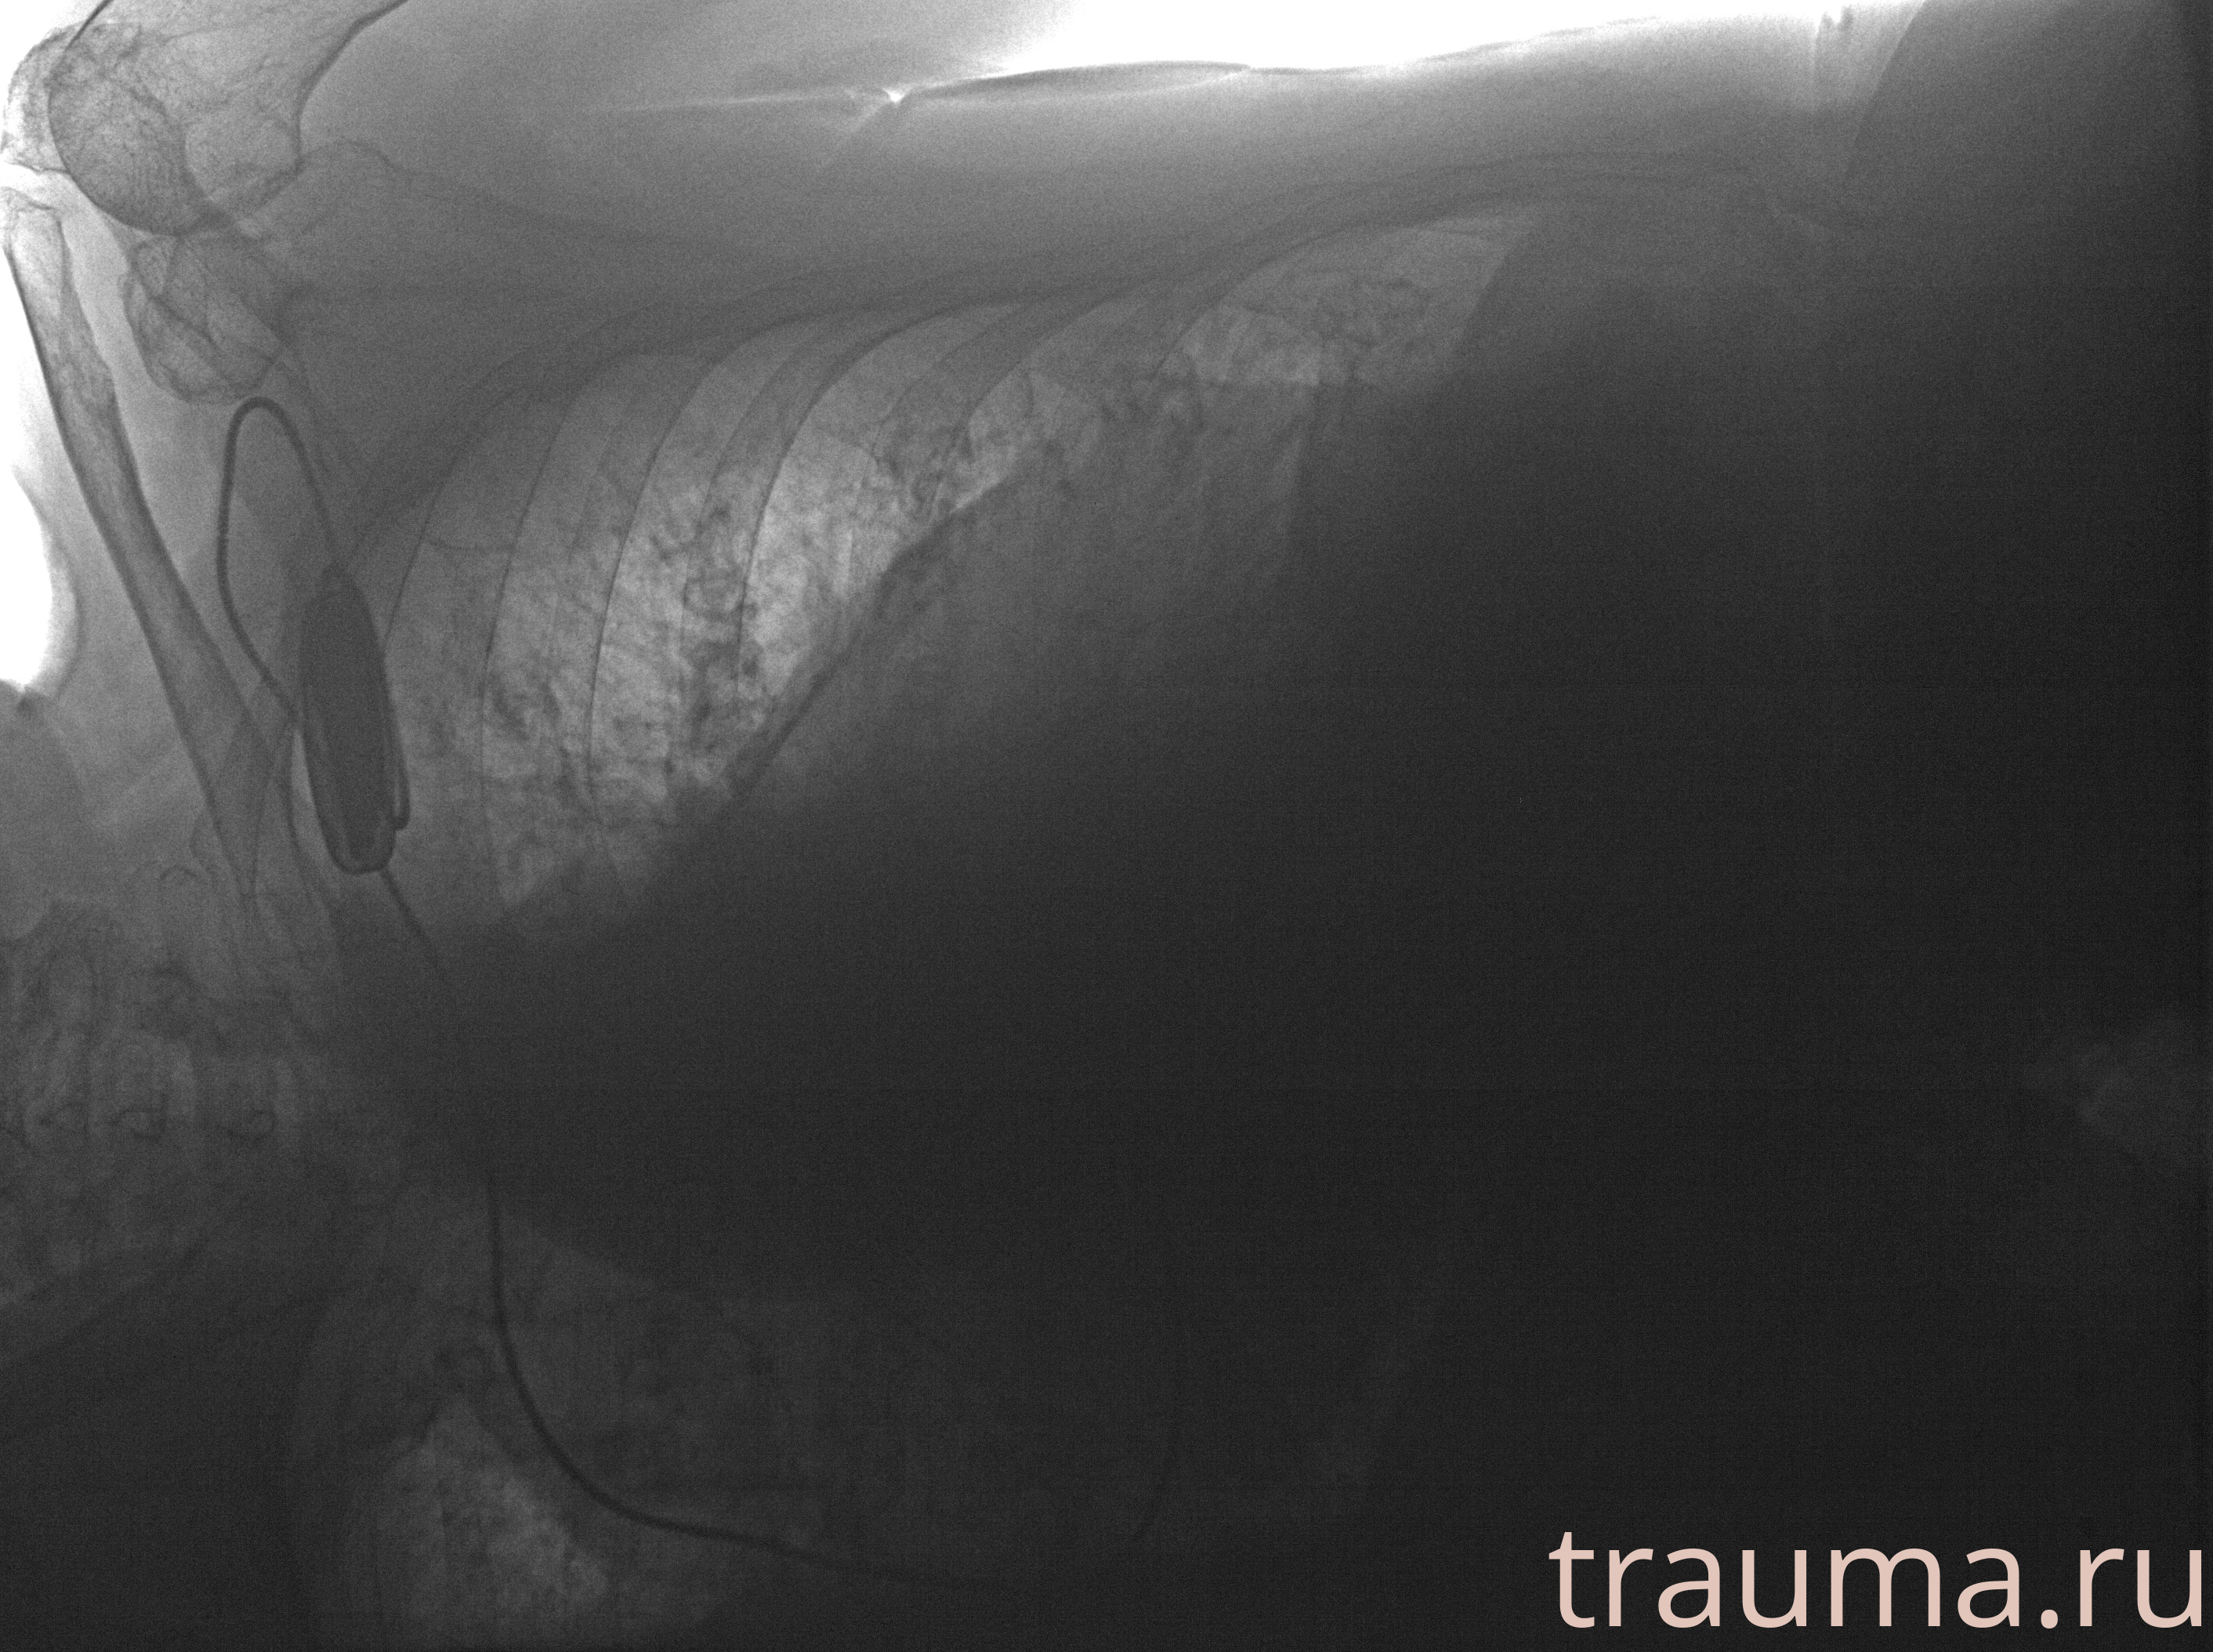

Рентгенограммы

Рентген на дому: по вашему адресу приезжает врач-рентгенолог, травматолог-ортопед с мобильным рентгеновским аппаратом, проводит диагностику травмы или заболевания, делает необходимые рентгенограммы, дает рекомендации по дальнейшему лечению. Получить качественные снимки в домашних условиях возможно благодаря уникальной методике, разработанной МосРентген Центром для института  Склифосовского

при переломе шейки бедра и пневмонии от компании МосРентген Центр - партнера Института имени Склифосовского